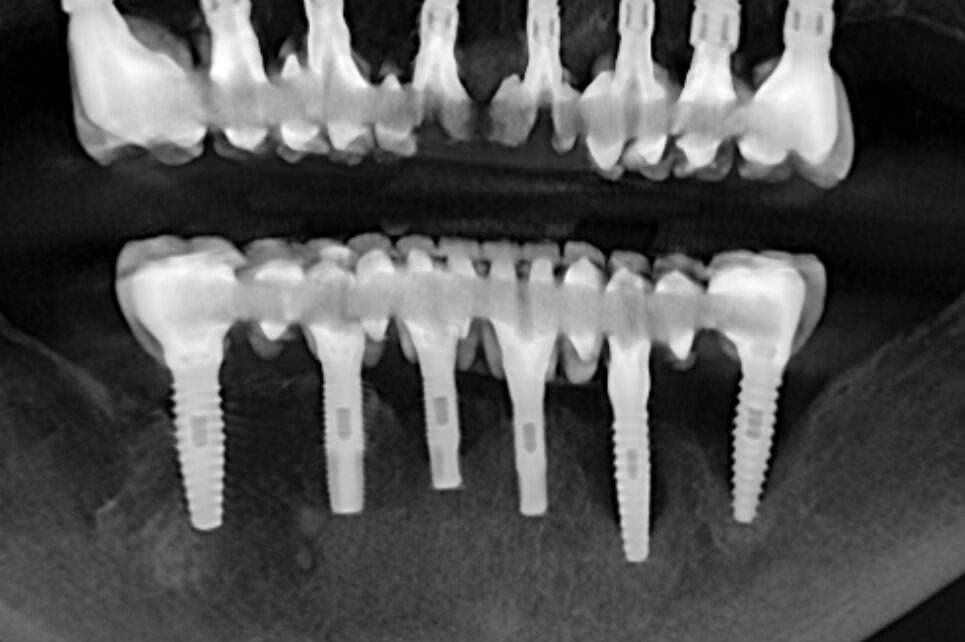

🦷 Antes, durante y después: así mejoró este caso de periimplantitis en 2 años 🦷